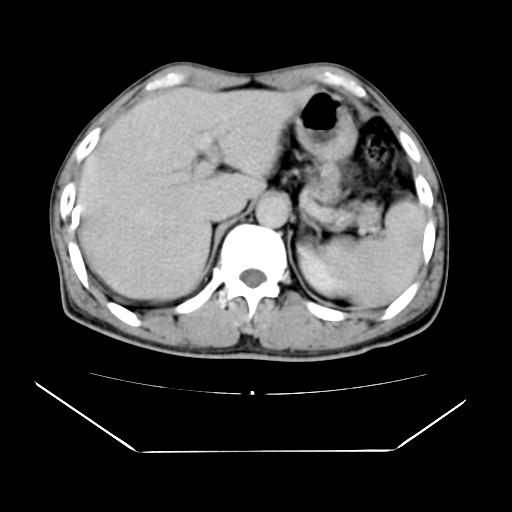

男性,55岁,外院体检afp明显升高,但b超未发现异常,否认乙肝病史。来我院ct增强。有延时扫描。

肝脏右叶动脉期可见低密度影,至延迟期被充填,考虑血管瘤可能性大。

肝右叶病灶

不排除肝右叶肝癌可能。

这个不是肝右静脉吗,这么大的病灶b超不可能发现不了吧

如果这个是癌灶的话则下腔静脉有瘤栓可能

肝6段血管瘤

血管瘤可能性大。

是肝右静脉吧

考虑肝右静脉影。